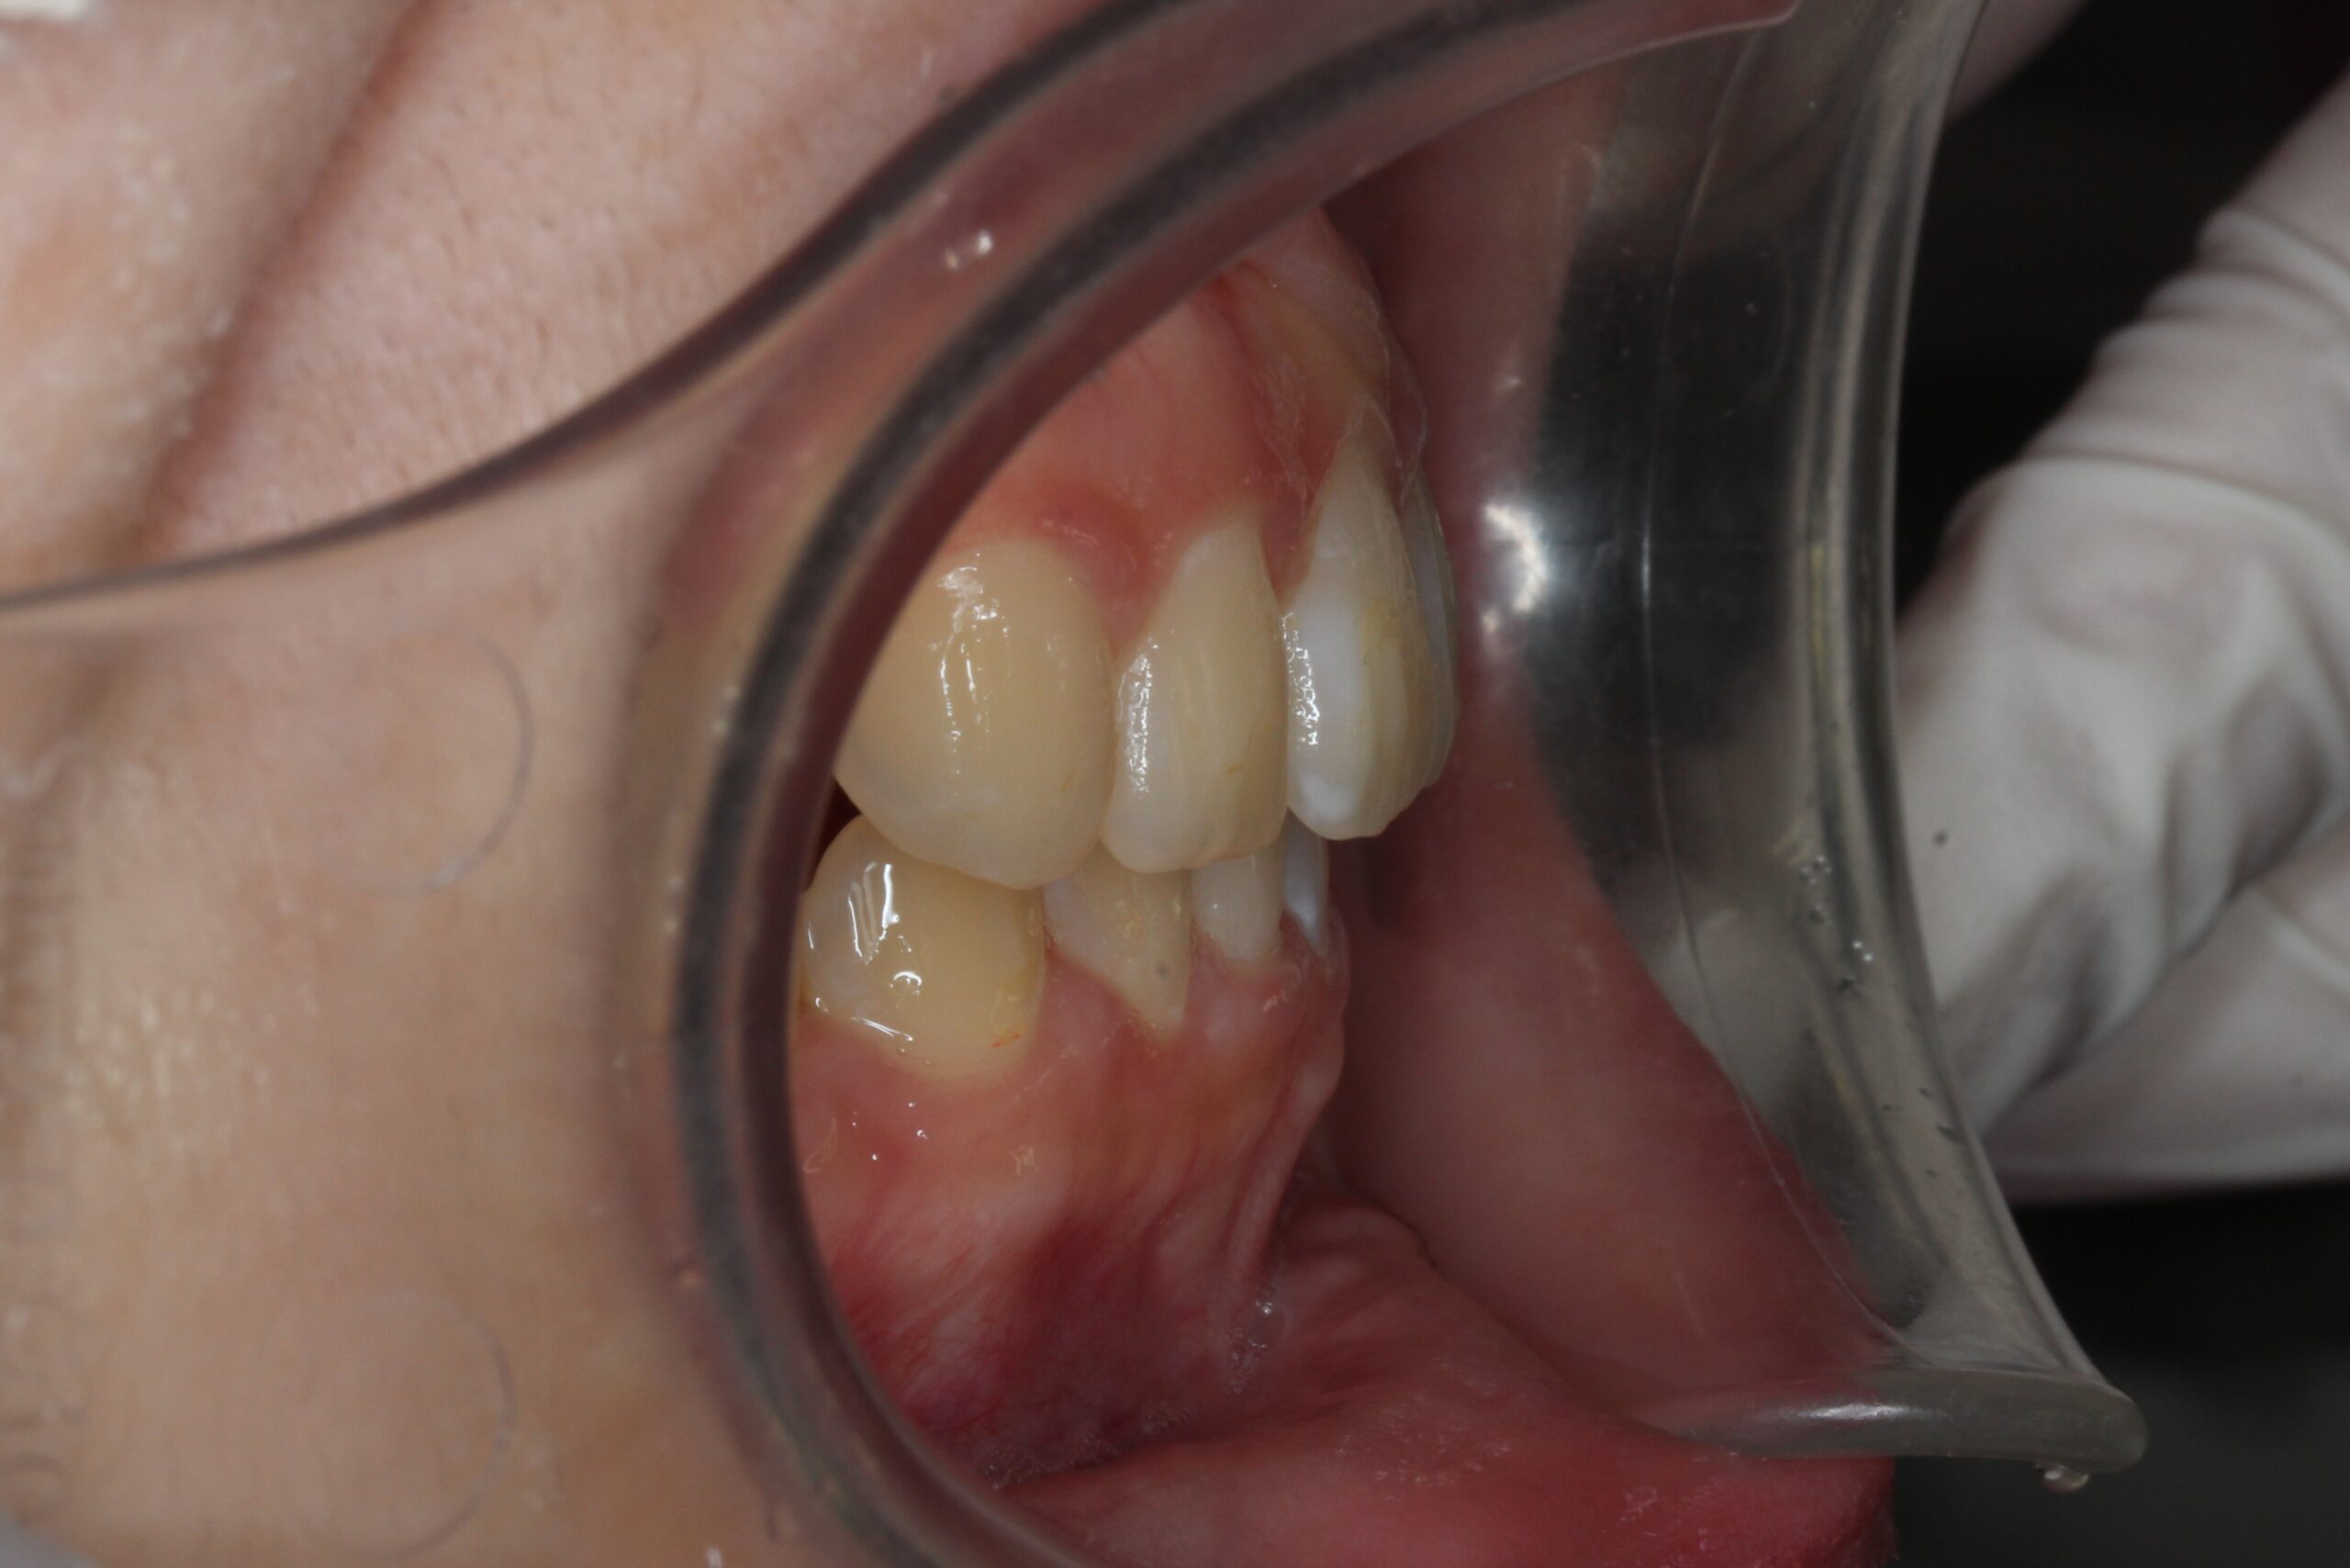

矯正術前:右側

矯正術後:右側